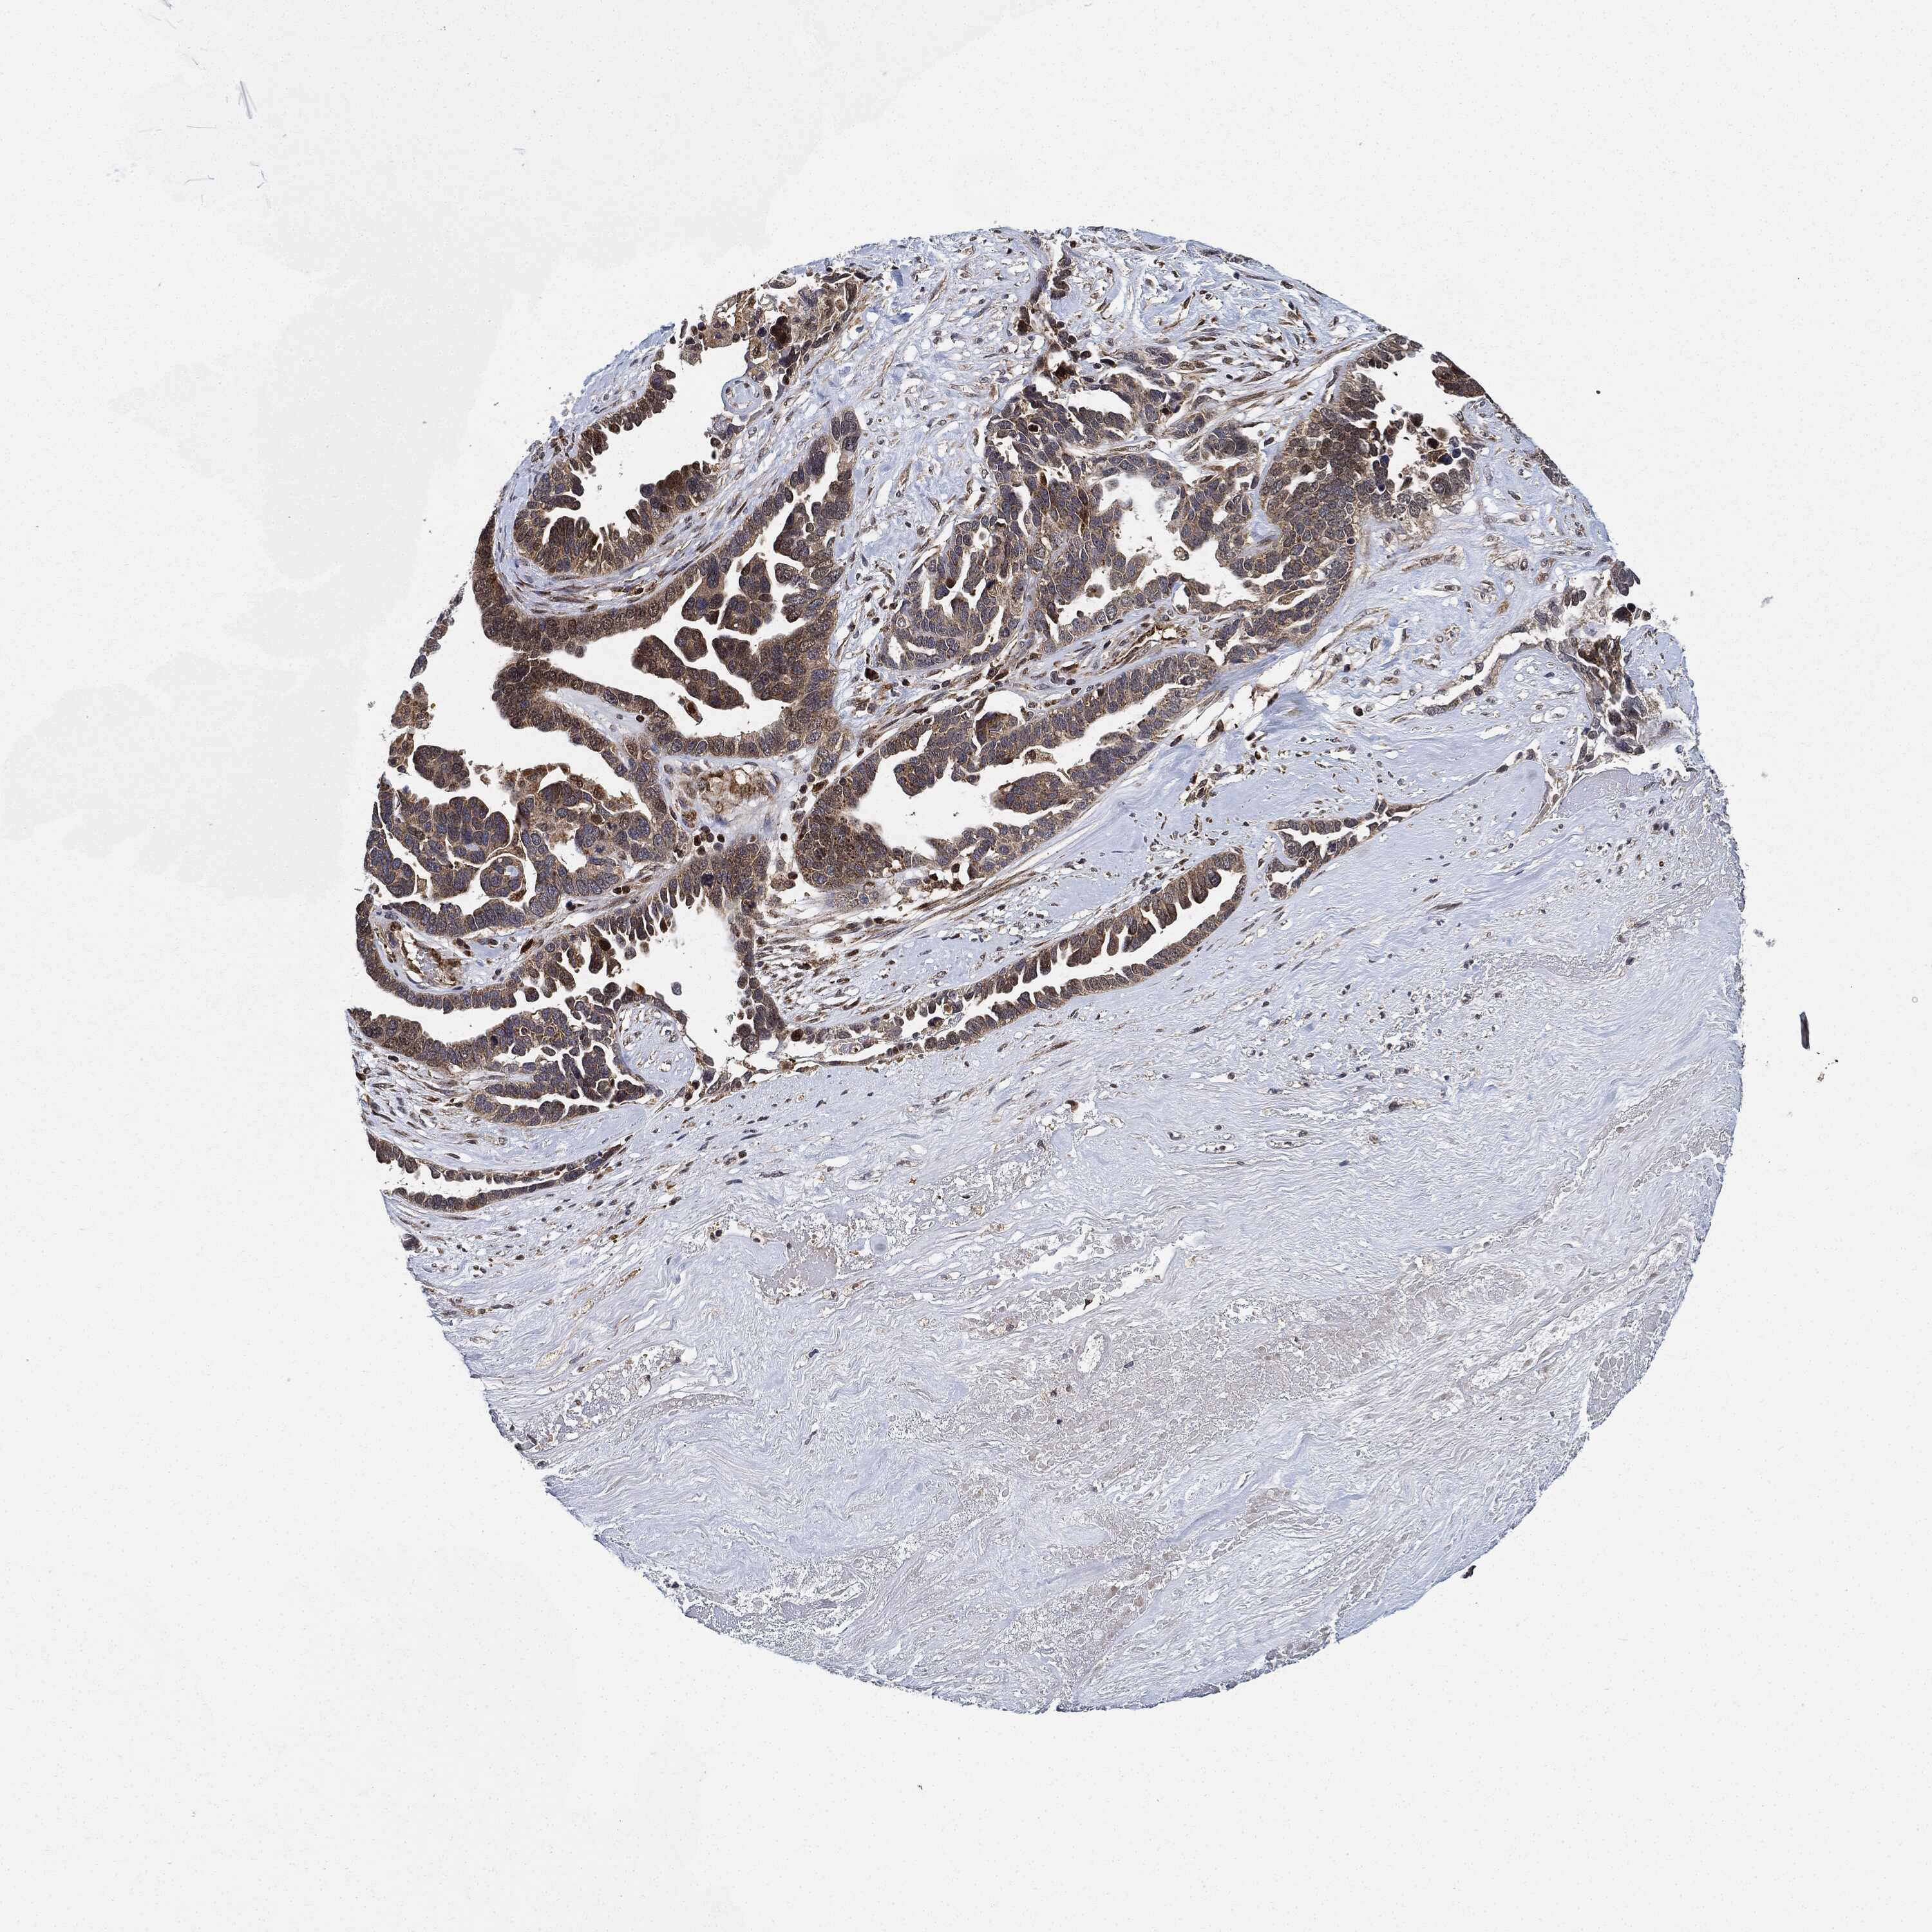

OVARIAN CANCER - Protein expressioni

A mouse-over function shows sample information and annotation data. Click on an image to view it in a full screen mode. Samples can be filtered based on level of antibody staining by selecting one or several of the following categories: high, medium, low and not detected. The assay and annotation is described here.

Note that samples used for immunohistochemistry by the Human Protein Atlas do not correspond to samples in the TCGA dataset.

Antibody stainingi

Antibody staining in the annotated cell types in the current human tissue is reported as not detected, low, medium, or high, based on conventional immunohistochemistry profiling in selected tissues. This score is based on the combination of the staining intensity and fraction of stained cells.

Each image is clickable and will lead to virtual microscopy that enables deeper exploration of all samples and also displays staining intensity scores, fraction scores and subcellular localization as well as patient and tissue information for each sample.

Antibody HPA002633

Carcinoma, endometroid

Cystadenocarcinoma, serous, NOS

Cystadenocarcinoma, mucinous, NOS

Carcinoma, NOS